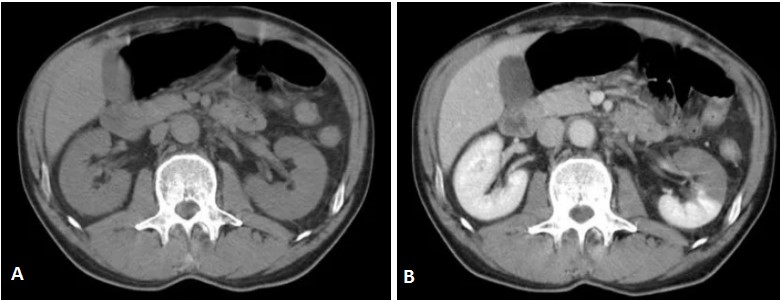

КТ ретроперитонеального фиброза: Изображения и диагностика